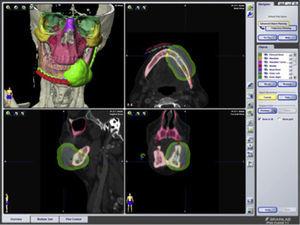

Tras una resección tumoral se precisa de una información exacta para definir correctamente la forma y posición de la reconstrucción y predecir los resultados postoperatorios14,15. Los softwares de diseño y modelado (CAD-CAM) han mejorado la estrategia quirúrgica en cirugía reconstructiva del esqueleto craneomaxilofacial (fig. 2). El tiempo adicional invertido en el proceso de planificación se ahorra durante la cirugía gracias a una interpretación más fácil de la situación clínica, y a poder realizar en tiempo real un control de calidad intraoperatorio del proceso reconstructivo2.

Planificación virtual de los márgenes de resección de un carcinoma epidermoide con afectación mandibular y planificación de la reconstrucción.

Figura 2.

(0,17MB).